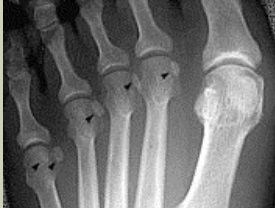

Describe the alignment of metatarsal 2 | There is no angulation nor displacement of the distal segment relative to the proximal segment. |

Describe the alignment of metatarsal 3 | The distal segment is displaced laterally (50% apposition) and angulated medially. |

Describe the alignment of metatarsal 4 | The distal segment is displaced laterally (75% apposition) but there is no apparent angulation. |

Describe the tubulation of the metatarsals | Metatarsals are overtubulated - decreased girth. |